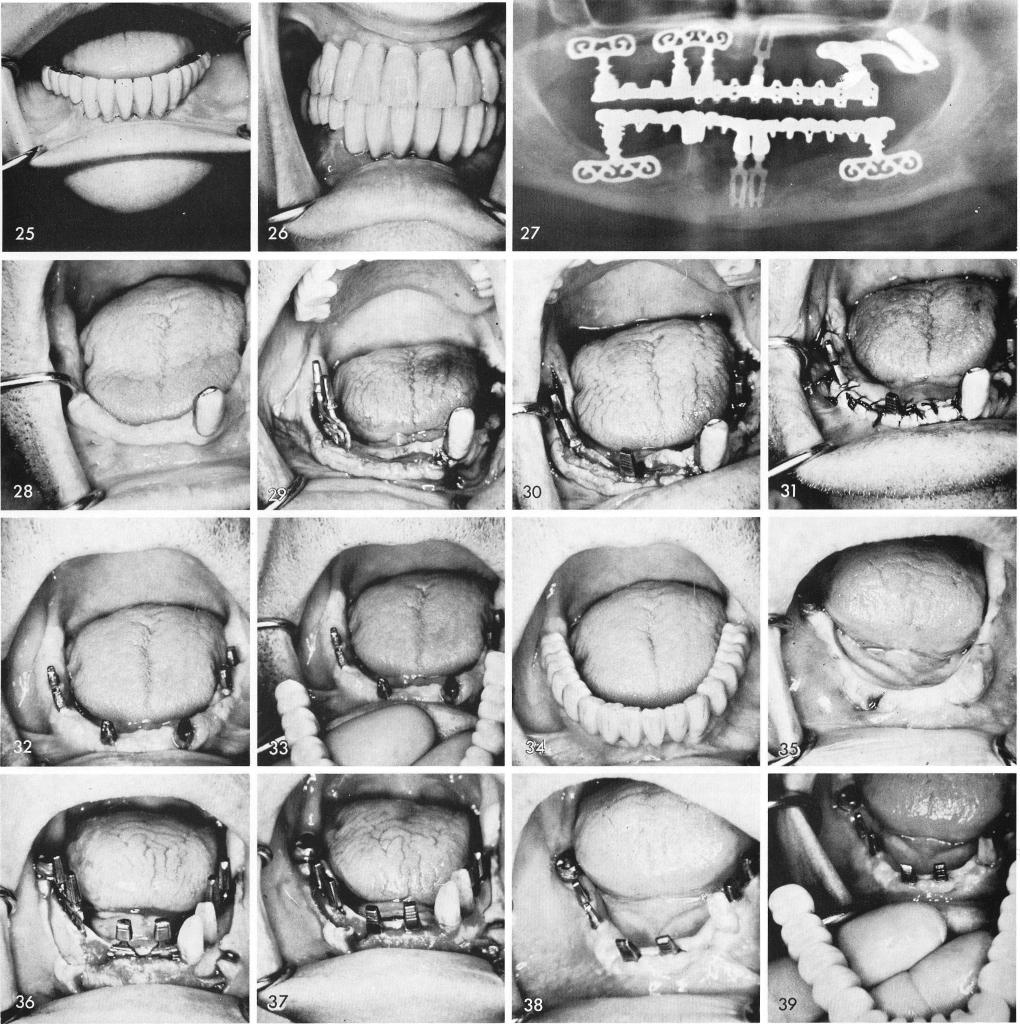

to remove the remaining left tooth, fig. 24, and the prosthesis was cemented, figs. 25, 26. A final x-ray shows the healing of bone inside the large sockets, fig. 27.

Even in knife edge ridges with only a single tooth remaining, fig. 28, blades can often solve the problems, figs. 29, 30, 31. After healing and preparation of the remaining left cuspid for a full crown restoration, fig. 32, the fabricated prosthesis is adjusted and cemented, figs. 33, 34. A long span existed between the two teeth on the left and the third molar on the right side of the arch, fig. 35. Blades were inserted, figs. 36, 37, and during the healing it was decided to remove